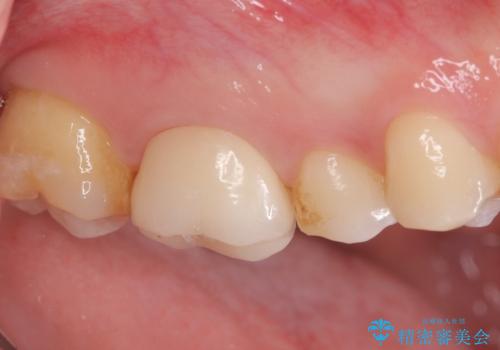

【奥歯のセラミッククラウン】他院で根管治療も必要だといわれた。

もともと症状はない状態でしたが、治療後は少しずつ病変の大きさが小さくなっているのを確認できます。

以前治療した際のむし歯が大きく、長い年月の間に少しずつ歯髄が死んでしまったと思われる状況でした。

長期にわたる炎症により、口蓋根尖は吸収を起こしていたため、MTAにて充填しています。